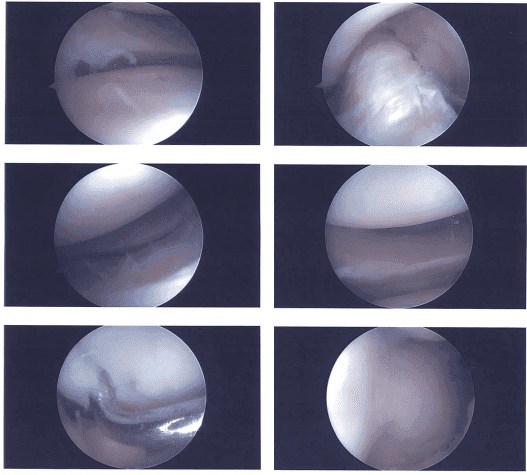

Microfractura (reparación del menisco, endoscopía de rodilla), meniscectomía La artroscopia de rodilla es el proceso de utilizar un artroscopio para detectar daños generales en los tejidos de la rodilla y curar dolencias específicas.

Documentación de imágenes

Estado tras la meniscectomía artroscópica de rodilla derecha, microfractura condroplastia y fijación artroscópica asistida de la meseta tibial con cirugía de cemento fosfato de calcio (subcondroplastia). También se le realizó una cirugía artroscópica en el hombro izquierdo.